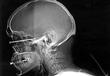

نجح فريق طبي بمدينة الملك سعود الطبية بالمملكة العربية السعودية في انقاذ مقيم أسيوي فقد إحدى عينيه بعد تعرضه لإصابة أثناء عمله ودخول مسمار داخل العين تم استخراجه ليستعيد بصرَه، وفقاً لفيديو نشرته صحيفة سبق السعودية اليوم الأربعاء.

وأوضح الدكتور تركي التركي، استشاري جراحة القرنية والليزك ورئيس قسم العيون بمدينة الملك سعود الطبية، أنه تم حقن عين المريض بمضادات الالتهاب والمضادات الحيوية، ومن ثم ترميم الأجزاء الداخلية للعين في عمليات لاحقة.

وأفادت صحيفة سبق السعودية أن المريض يتعافى من إصابته بعد أن تم استخراج المسمار الفولاذي المقوس من عينه، فيما لم تذكر المزيد من التفاصيل حول كيفية وقوع الحادث أو المدة التي يحتاجها كي يستعيد بصره بشكل كامل.